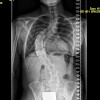

Seit einigen Jahren hat sich die Situation deutlich verändert. Das diesjährige Röntgenbild zeigt einen thorakalen Cobb-Winkel von ca. 80–90°. Im MRT wurde eine schwere S-förmige thorakolumbale Skoliose festgestellt mit degenerativen Bandscheibenschäden von BWK 11 bis LWK 5, Osteochondrose Typ Modic 2 bei LWK 3/4 und beginnender Facettengelenksdegeneration rechts. Schmerzen im Lendenbereich mit Schmerzwert ~7, vor allem morgens und nach längerem Sitzen oder Stehen.